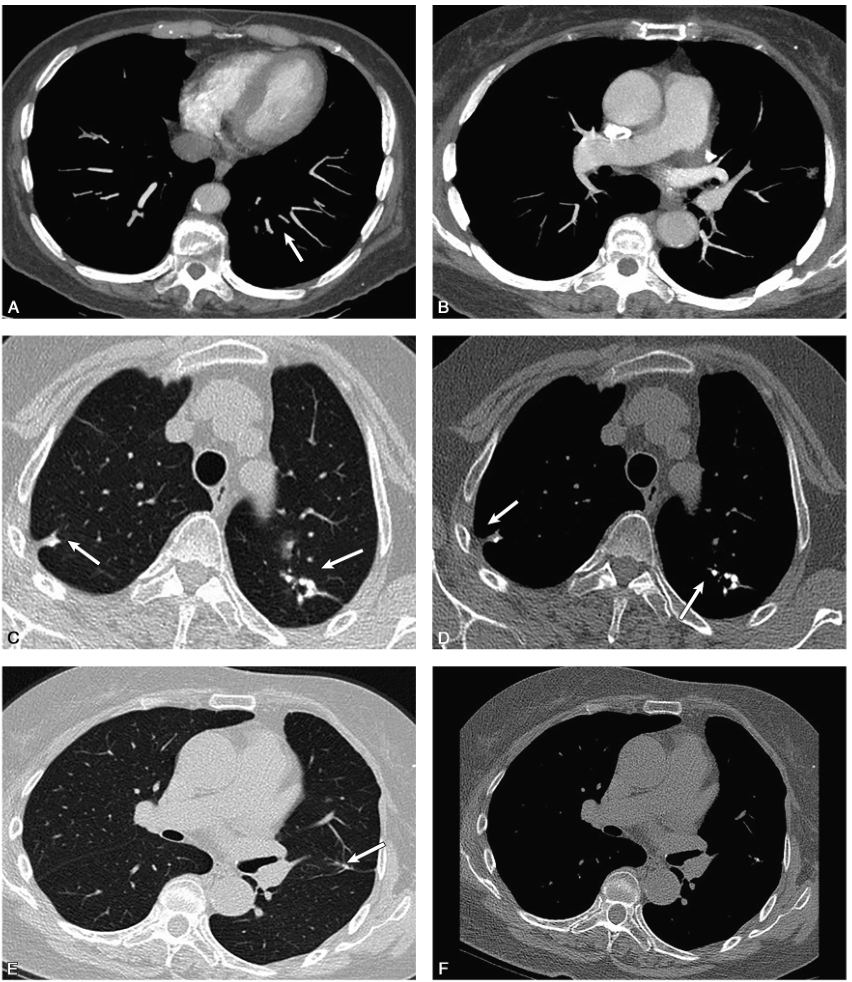

胸部CT:两肺多发结节及纤维条索影,部分伴钙化,考虑陈旧性病变,左肺上叶舌段结节(图1A~D)。

,右肺下叶背段可见磨玻璃影(C),左肺上叶舌段可见部分实性结节影(D.jpg)

图1胸部薄层CT扫描:双肺上叶尖段多发毛玻璃影和多发陈旧性钙化灶伴粗大毛刺(A、B),右肺下叶背段可见磨玻璃影(C),左肺上叶舌段可见部分实性结节影(D);入院后复查肺动脉CTA示左下肺动脉多发残留血栓(E、F)(白箭)

肺动脉CTA检查:左下肺动脉局部可见少许结节状充盈缺损(图1E、F)。